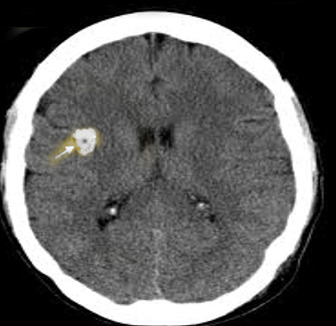

The white spot (see arrow) is a brain cysticercosis caused by a tape worm known as Taenia Solium. Poor dead worm.